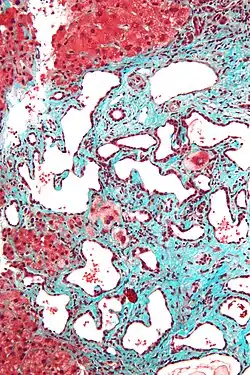

Histopathology of a bile duct hamartoma, high magnification, H&E stain. It shows typical features of bile duct hamartoma: Small to medium sized, irregularly shaped bile ducts lined by bland cuboidal epithelium (may also be flattened). Prominent intervening collagenous stroma. Bile ducts containing eosinophilic debris (may also contain inspissated bile) -

Micrograph of a bile duct hamartoma. Trichrome stain. Intermediate magnification -

Low magnification micrograph of a bile duct hamartoma. Trichrome stain. -